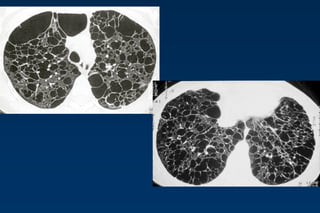

Cystic lung disease

Lung cysts are defined as radiolucent areas with a

wall thickness of less than 4mm.

Langerhans cell histiocytosis

Lymphangiomyomatosis complicated by pneumothorax

Cystic lung diseases